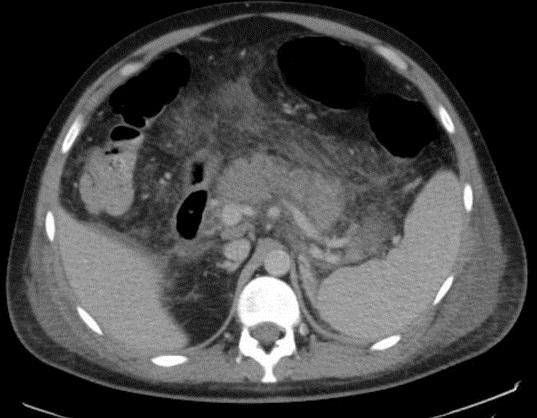

Image radiologique TDM

arteriel phase d'une pancreatite necrosant

hemoragique : Pancreas en volumineuse , presence des

foyers de necrose , hemorragique et exudative a

hypodense ,absence ou moindre de rehaussement situe

intra et extra pancreatique |